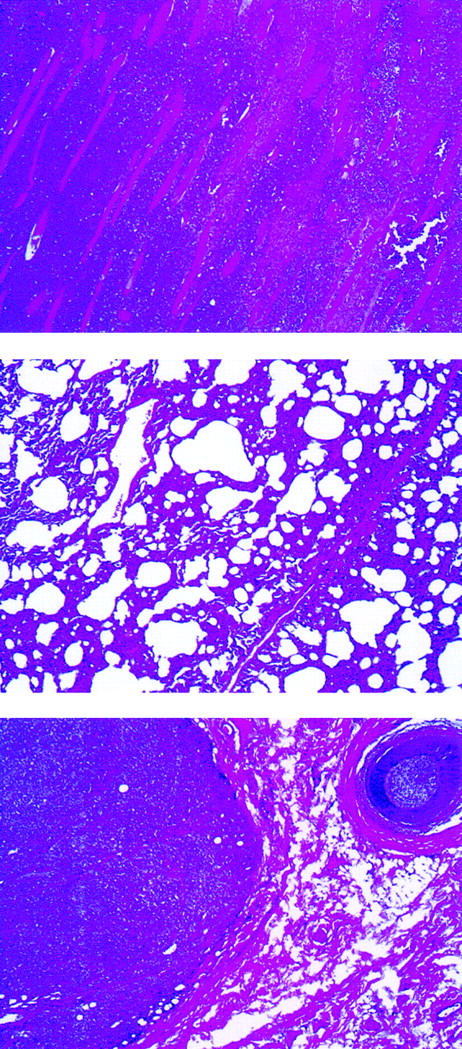

Histologic examination of rabbit tissues revealed diffuse mixed lymphocyte infiltrates involving many organs. An example is shown in Figure 2 of rabbit C2182, in which poorly differentiated neoplastic cells were predominant in skeletal muscle and lungs. Subcutaneous infiltrates were observed in animals C2182 (Figure2, bottom panel) and in rabbits C2174 and C2178 (data not shown).

Abnormal findings of lymphomatous rabbit C2182.

Lymphomatous cell infiltration in the abdominal muscles (top), lung (center), and subcutaneous mass (bottom) (original magnification, ×40).